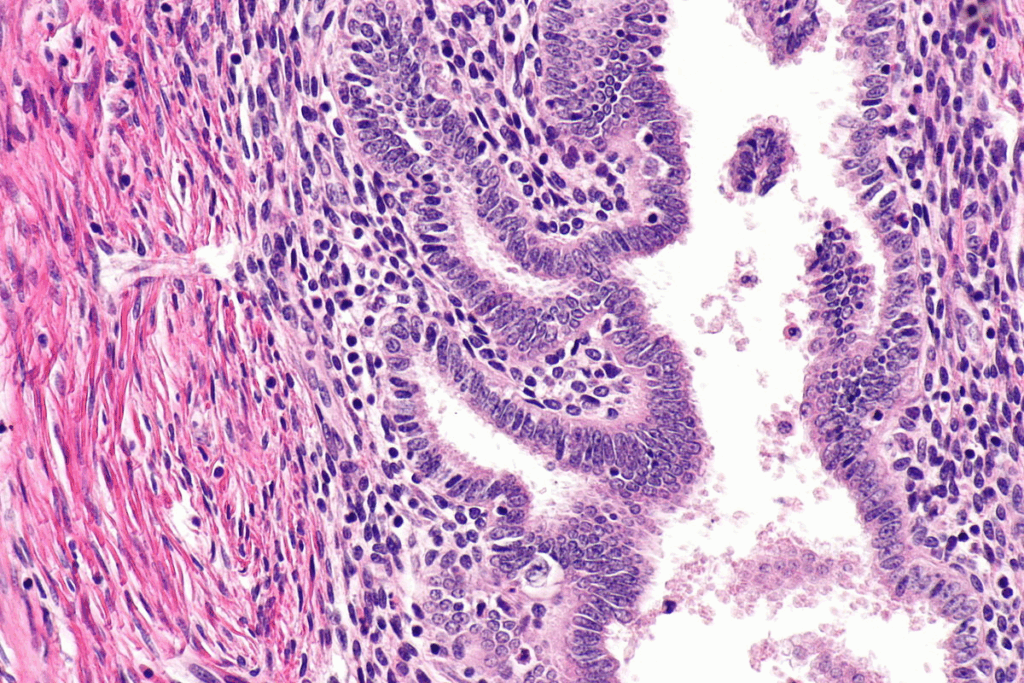

Uterine fibroids, or leiomyomas, are non-cancerous tumors in the uterus. They can cause symptoms that might need surgery. We’ll look at what these growths are, symptoms that might need surgery, and how doctors decide on surgery.

Uterine fibroids are non-cancerous growths in or around the uterus. They can be different sizes, numbers, and locations. These growths are common among women of reproductive age. The exact cause is unknown, but genetics, hormones, and environment play a role.

Myomectomy is a surgery that removes fibroid tumors but keeps the uterus. This makes it a top choice for women who want to keep their fertility options open. It’s key for those with uterine fibroids who want to stay fertile.